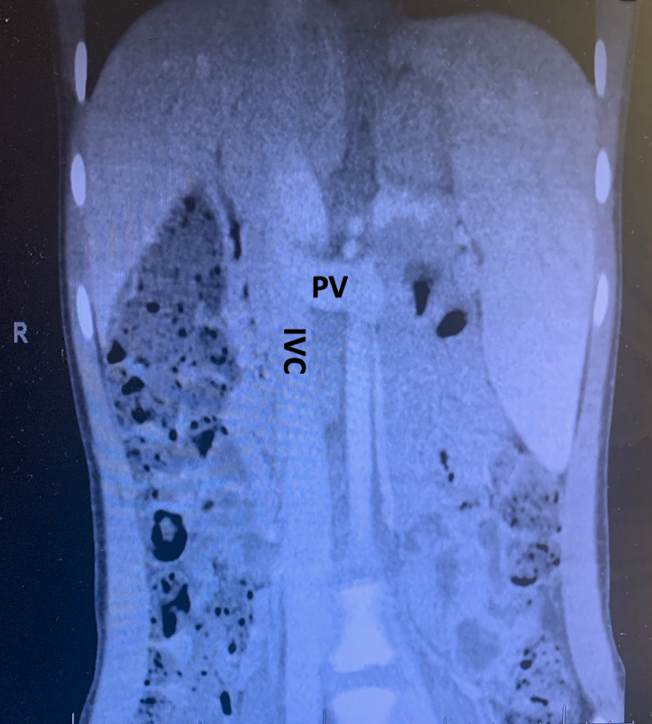

Case report: A 8-year old female child who was diagnosed with CAPV was referred to our centre for further evaluation. She was a full-term baby and doing well till 4years of age when she had near fainting. During evaluation she had elevated liver function test, splenomegaly and imaging revealed CAPV with shunting. Her family reported decline in her academic performance over past few years. On index visit her total bilirubin was 1.4 mg/dL, AST 40 IU/L, ALT 29 IU/L and serum ammonia 122 ug/dL with no evidence of hepatopulmonary syndrome. The CECT abdomen revealed common trunk of splenic vein and SMV, directly draining into IVC with prominent hepatic artery (Figure 1). She received deceased donor liver transplant from brain dead donor (Figure 2) and postoperative course was uneventful. Liver function has remained stable with patent PV and hepatic artery. Histology of the native liver showed absent PV with nodular liver parenchyma without cirrhosis.